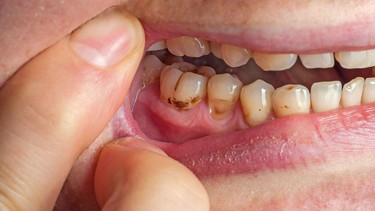

- Sâu răng sữa tiến triển: Là nguyên nhân phổ biến nhất, do vi khuẩn trong mảng bám răng tiết acid phá hủy men và ngà răng.

- Khám lâm sàng: Đánh giá mức độ đau, phản ứng với nhiệt độ, kiểm tra sưng nướu và màu sắc răng.